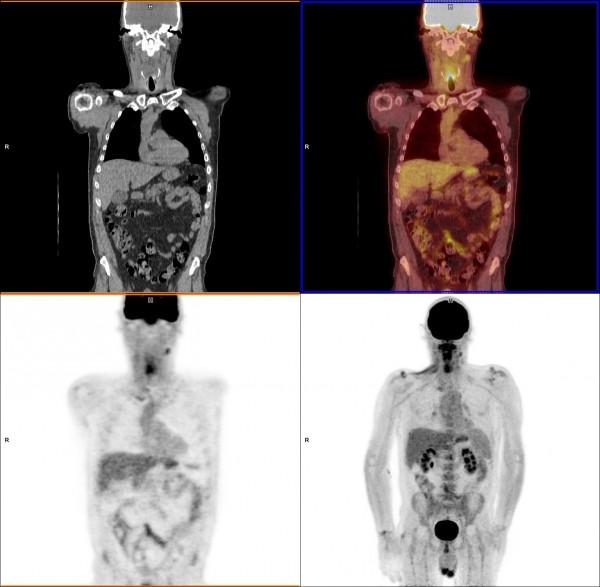

Single-photon emission computerized tomography (SPECT) imaging is a nuclear imaging technology (also referred to as molecular imaging) that produces images showing how organs work.